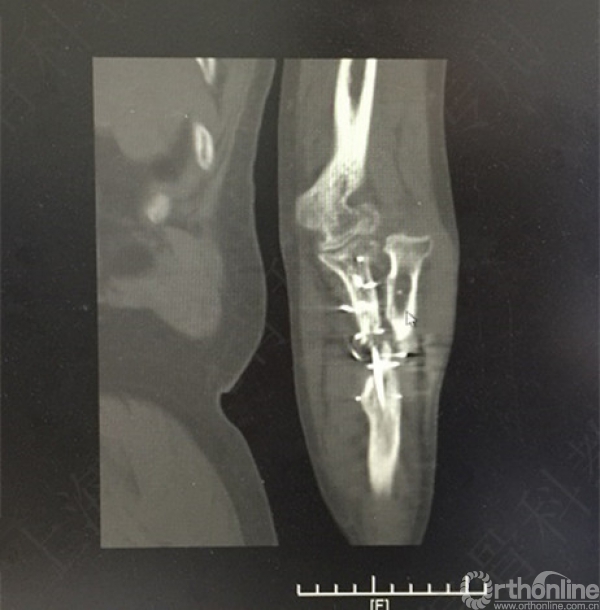

患者左尺桡骨多发骨折伴肘关节脱位,术后2年,桡神经损伤,左拇指伸受限。

X线及CT示:左尺桡骨骨不连,尺骨力线差,成角,桡骨头脱位,创伤性关节炎。

患者择期行左尺桡骨取原内固定+切开复位内固定术+髂骨异体骨植骨+桡骨头切除术。

术后X线片示:左尺桡骨骨不连术后,对位对线可,内固定牢靠,桡骨头切除,肘关节在位。

医方第一次术后,未能纠正骨折力线,未发现桡骨头脱位,手术方式和操作欠妥当。存在对疾病评估不足,漏诊,手术方式不当,手术操作不当,术后并发症观察及处理不当等过失。